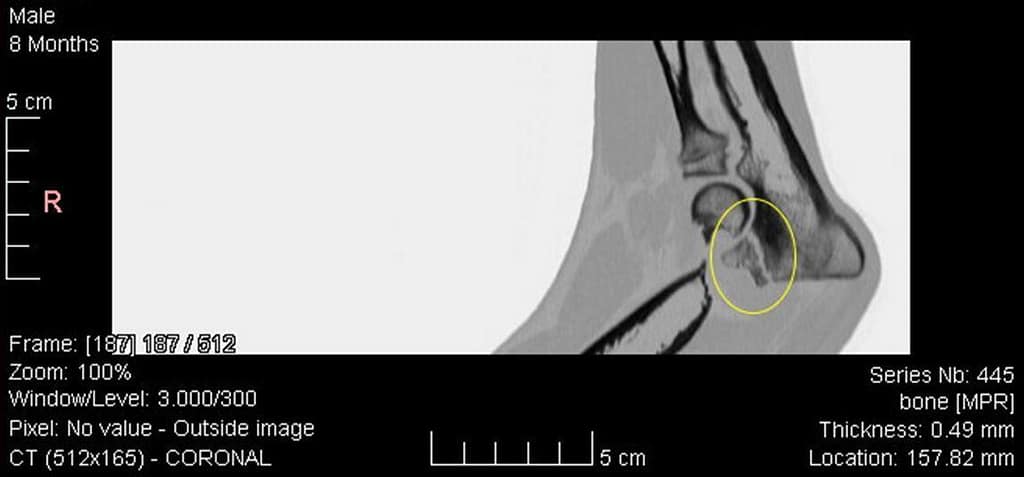

- OCD (Osteochondritis dissecans): het loslaten van een stukje kraakbeen van de bovenarm.

- LPC (Los processus coronoïdeus): het loslaten van een stukje bot van de ellepijp.

- LPA (Los processus anconeus): het loslaten van een stukje bot op een andere plaats van de ellepijp.

- Incongruentie: een niet goed “passend” gewricht door een te lange of te korte ellepijp ten opzichte van het spaakbeen.